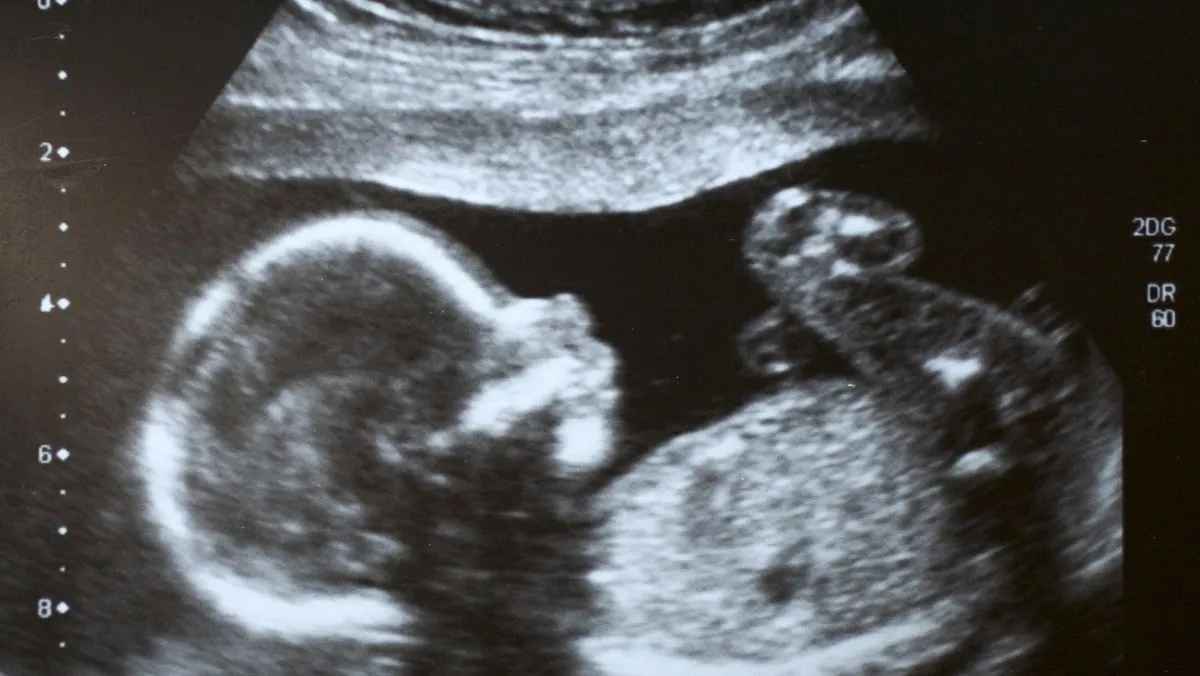

Para ilmuwan dan pakar etika masih memperdebatkan penggunaan teknologi yang memungkinkan pengeditan gen pada sel telur, sperma, dan embrio manusia. Perdebatan ini mengemuka seiring berkembangnya CRISPR-Cas9, teknologi yang dinilai mampu mengubah DNA bayi yang belum lahir.

CRISPR-Cas9 kerap digambarkan sebagai “gunting molekuler” yang dapat secara selektif membuang bagian-bagian yang tidak diinginkan pada genom dan menggantinya dengan bagian DNA baru. Para ilmuwan menyebut teknologi ini berpotensi mencegah penyakit keturunan.

Meski menjanjikan, pihak yang menentang mengkhawatirkan efek yang belum diketahui terhadap generasi mendatang. Selain itu, mereka menilai terbuka kemungkinan di masa depan orang tua terdorong membayar untuk menambahkan sifat-sifat yang dianggap unggul, seperti kecerdasan tinggi atau kemampuan atletik, pada janin.